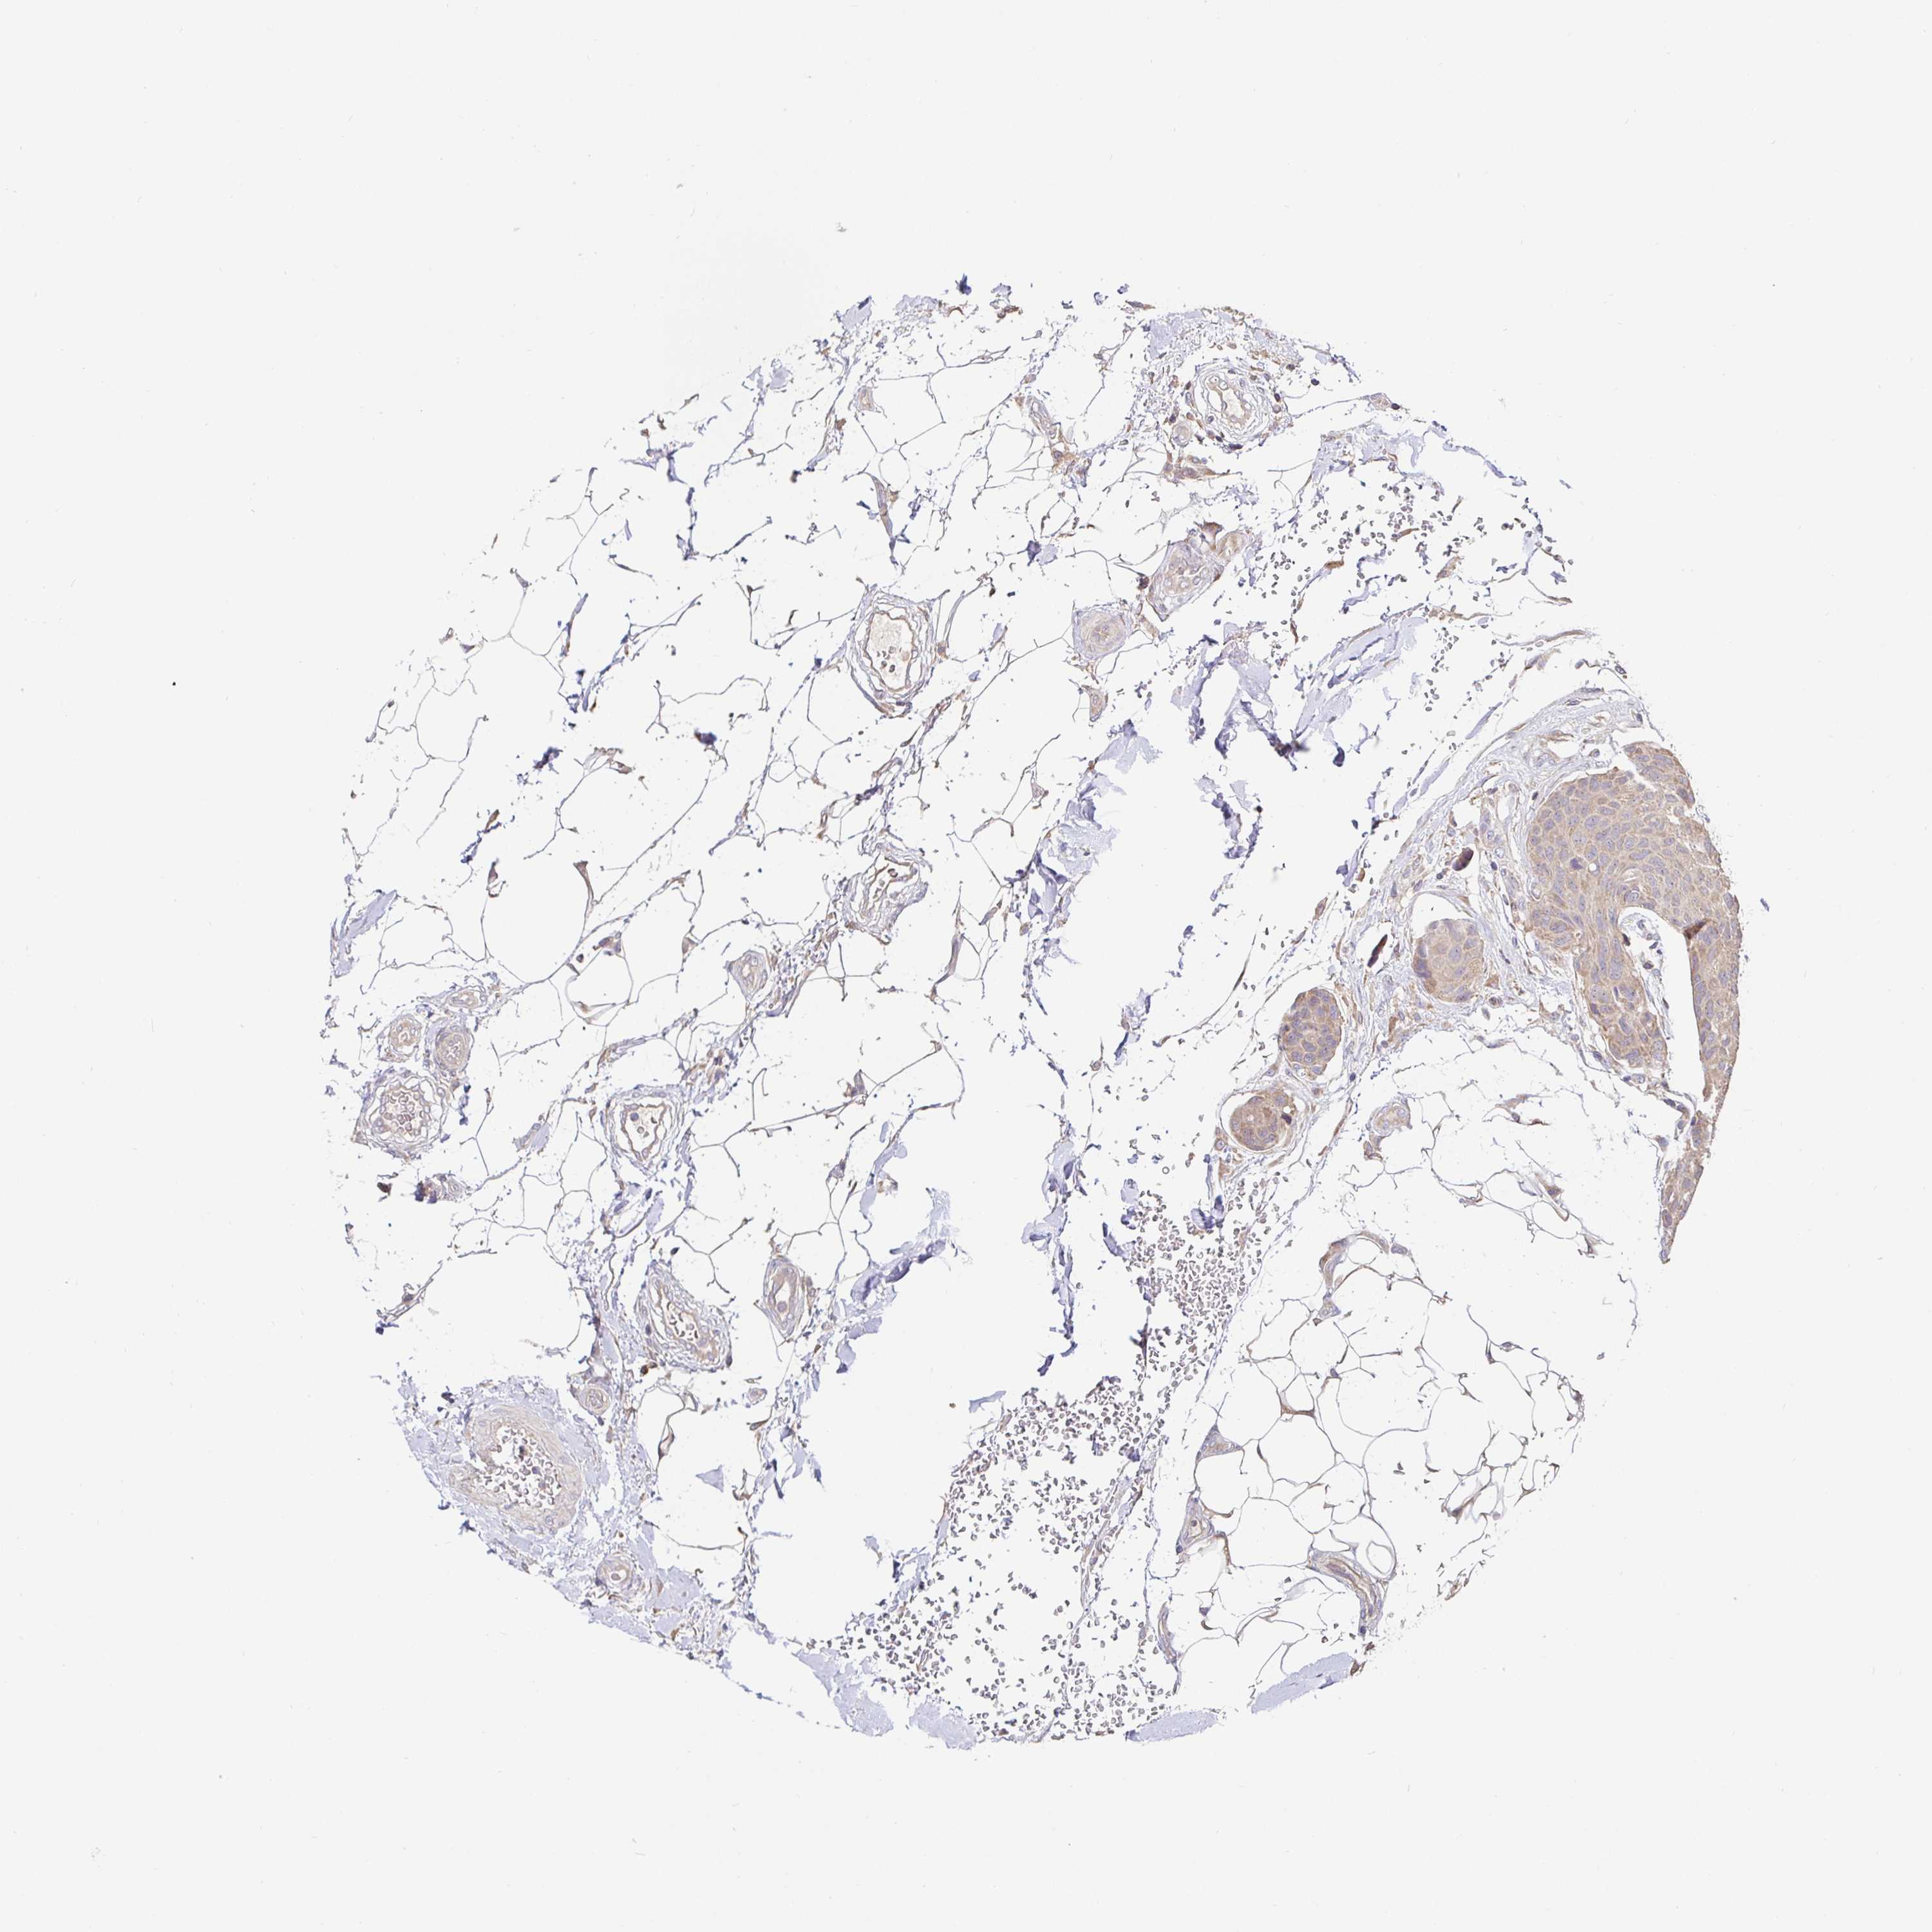

CANCER BREAST CANCER Show tissue menu

BRCA TCGA BRCA VALIDATION PROTEIN EXPRESSION